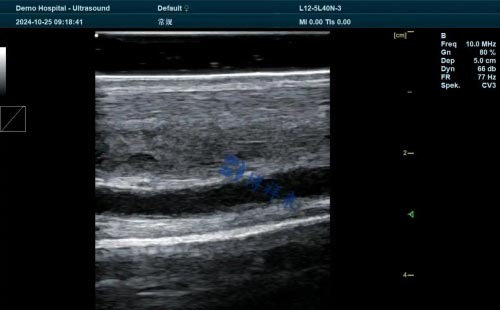

Many breeding farms around the world use ultrasound to monitor fetal viability and placental thickness in mares. While not a nutritional tool per se, ultrasonography provides reassurance that fetal development is progressing normally, indirectly reflecting nutritional adequacy.